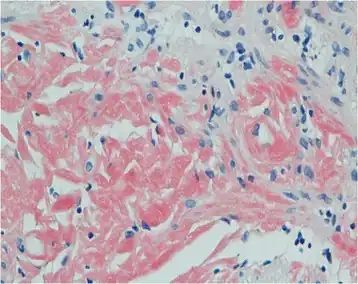

| Primary systemic amyloidosis initially presenting with digestive symptoms-gastric mucosa showed orange-red positivity | |

Both blood and the urine can be tested for the light chains, which may form amyloid deposits, causing disease. However, the diagnosis requires a sample of an affected organ.[5][8] Other diagnosis can be tissue biopsy. Tissue biopsy tests a tissue sample to look for amyloid deposits. The tissue is stained with red dye, and under a microscopic examination, amyloid proteins can be detected if the tissue turns an apple-green color. [9]